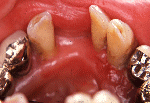

初診時初診時

一年後DT開始